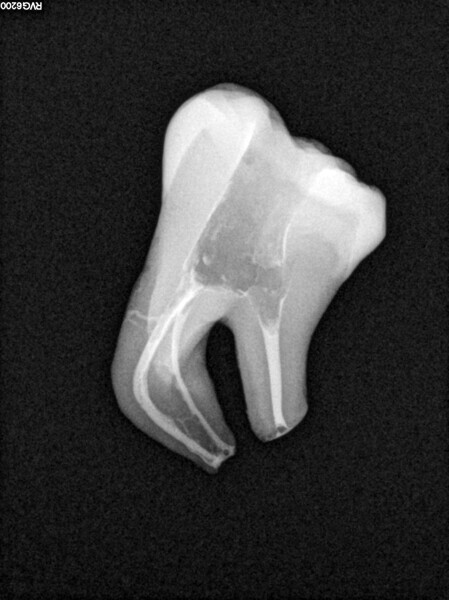

Micro-CT scans allowed clinicians to improve their knowledge about the complexity of the root canal system. This kind of image can help the clinician to understand the network of blood vessels inside the roots, especially in the molars. Comparison of micro-CT scans with radiographs available on the internet reveals that there is a visible difference between the micro-CT scans and the postoperative radiographs regarding the quality of obturation. The most visible difference is in the area of the apical delta and isthmuses between the canals. This difference led us to deduce that, even though root canal therapy procedures are very successful, a great deal of root canal space is not cleaned of hard-tissue debris and filled with obturation material.

The first trials of the LPE concept were performed on extracted human molars. Although the dynamics of fluid during root canal irrigation are completely different in vivo than in extracted teeth, these kinds of trials provide initial information about the procedure. Some of these teeth had apices closed with a coat of wax and composite resin to close the apical delta and simulate the periapical tissue. After creation of the access cavity, the pulp chamber was cleaned with continuous irrigation with 5.25% NaClO activated with a SkyPulse laser (Fotona) in AutoSWEEPS mode (20 Hz, 15 mJ). A 25/0.07 reciprocating file (Shenzhen Perfect Medical Instruments) was used to perform the pre-flaring procedure. After opening the coronal third, continuous irrigation with 5.25% NaClO activated with the laser was used to clear the debris for 30 seconds. After removing the debris, a #10 C-PILOT file (VDW) was used to establish apical patency, without forcing the file if possible. In some cases, apical patency was reached already at this stage of root canal preparation. In all cases, the second step of instrumentation was the preparation of the middle third with the same file, and the same irrigation procedure was performed. Subsequently, the C-PILOT file was used to reach the apical foramen. At this stage, apical patency was reached in most cases, but in some roots, there was no possibility of entering the apical foramen. The working length was confirmed with a radiograph with the hand file. Usually, the next procedure to be done is apical preparation, but the LPE concept is based on an enhanced irrigation protocol. Following this protocol, irrigation was performed for 5 minutes with continuous flow of 5.25% NaClO activated with the SkyPulse laser in AutoSWEEPS mode (20 Hz, 20 mJ) with a conical sapphire fibre. The next step was alternating irrigation with 17% EDTA for 30 seconds, with 5.25% NaClO for 30 seconds and with 17% EDTA for 30 seconds, all activated with AutoSWEEPS, followed by irrigation for another 5 minutes with 5.25% NaClO activated with AutoSWEEPS. In most cases, the next step after this stage of enhanced irrigation was the calibration of the apical constriction rather than apical preparation per se, but this step requires further investigation.

During the in vitro stage, different protocols for shaping the apical third were used. In some cases, only the coronal and middle thirds of the roots were prepared; in some cases, apical preparation was performed only with a #15 K-file; and in some cases, the preparation was performed with a 25/0.07 reciprocating file. No significant difference was observed in terms of the apical extrusion of the sealer and the homogeneity of the sealing material, but the sample size was too small to determine definitively whether the LPE enhanced irrigation protocol could replace the apical preparation stage.